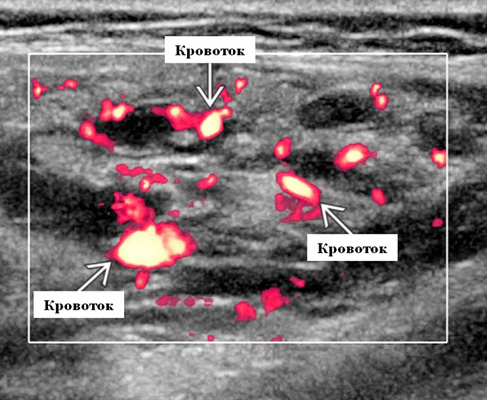

Серошкальное УЗИ. Узловая НХЛ. Одиночные или множественные увеличенные яйцевидные внутрипаротидные лимфатические узлы. Гомогенно гипоэхогенный по отношению к паренхиме околоушной железы. Сетчатый эхосигнал. Заднее акустическое усиление. Первичная паренхиматозная НХЛ. Рассеянный, неоднородный эхосигнал; нечеткие, гипоэхогенные, похожие на опухоль участки. В пунктате внутрикистозная или паренхиматозная кальцификация из-за конечной стадии воспалительного изменения. Небольшие кистозные области образуются из-за сдавления терминальных протоков лимфоидной гипертрофией. Множественные небольшие гипоэхогенные участки (представляют собой лимфоидные агрегаты), разбросанные на фоне ткани слюнной железы. Изменения могут имитировать хронический сиалоаденит и диагноз часто ставится при биопсии. На УЗИ необходимо искать аналогичное поражение других слюнных и слезных желез, фон синдром Шегрена, BLEL. Может иметь или не иметь перипаротидную и шейную лимфаденопатию

Цветной допплер. Узловая НХЛ. Выраженная центральная или внутриузловая гиперваскуляризация. Паренхима при неходжкинской лимфоме более диффузная железистая гиперваскуляризация. Васкуляризация от умеренной до выраженной в плохо очерченных образованиях.